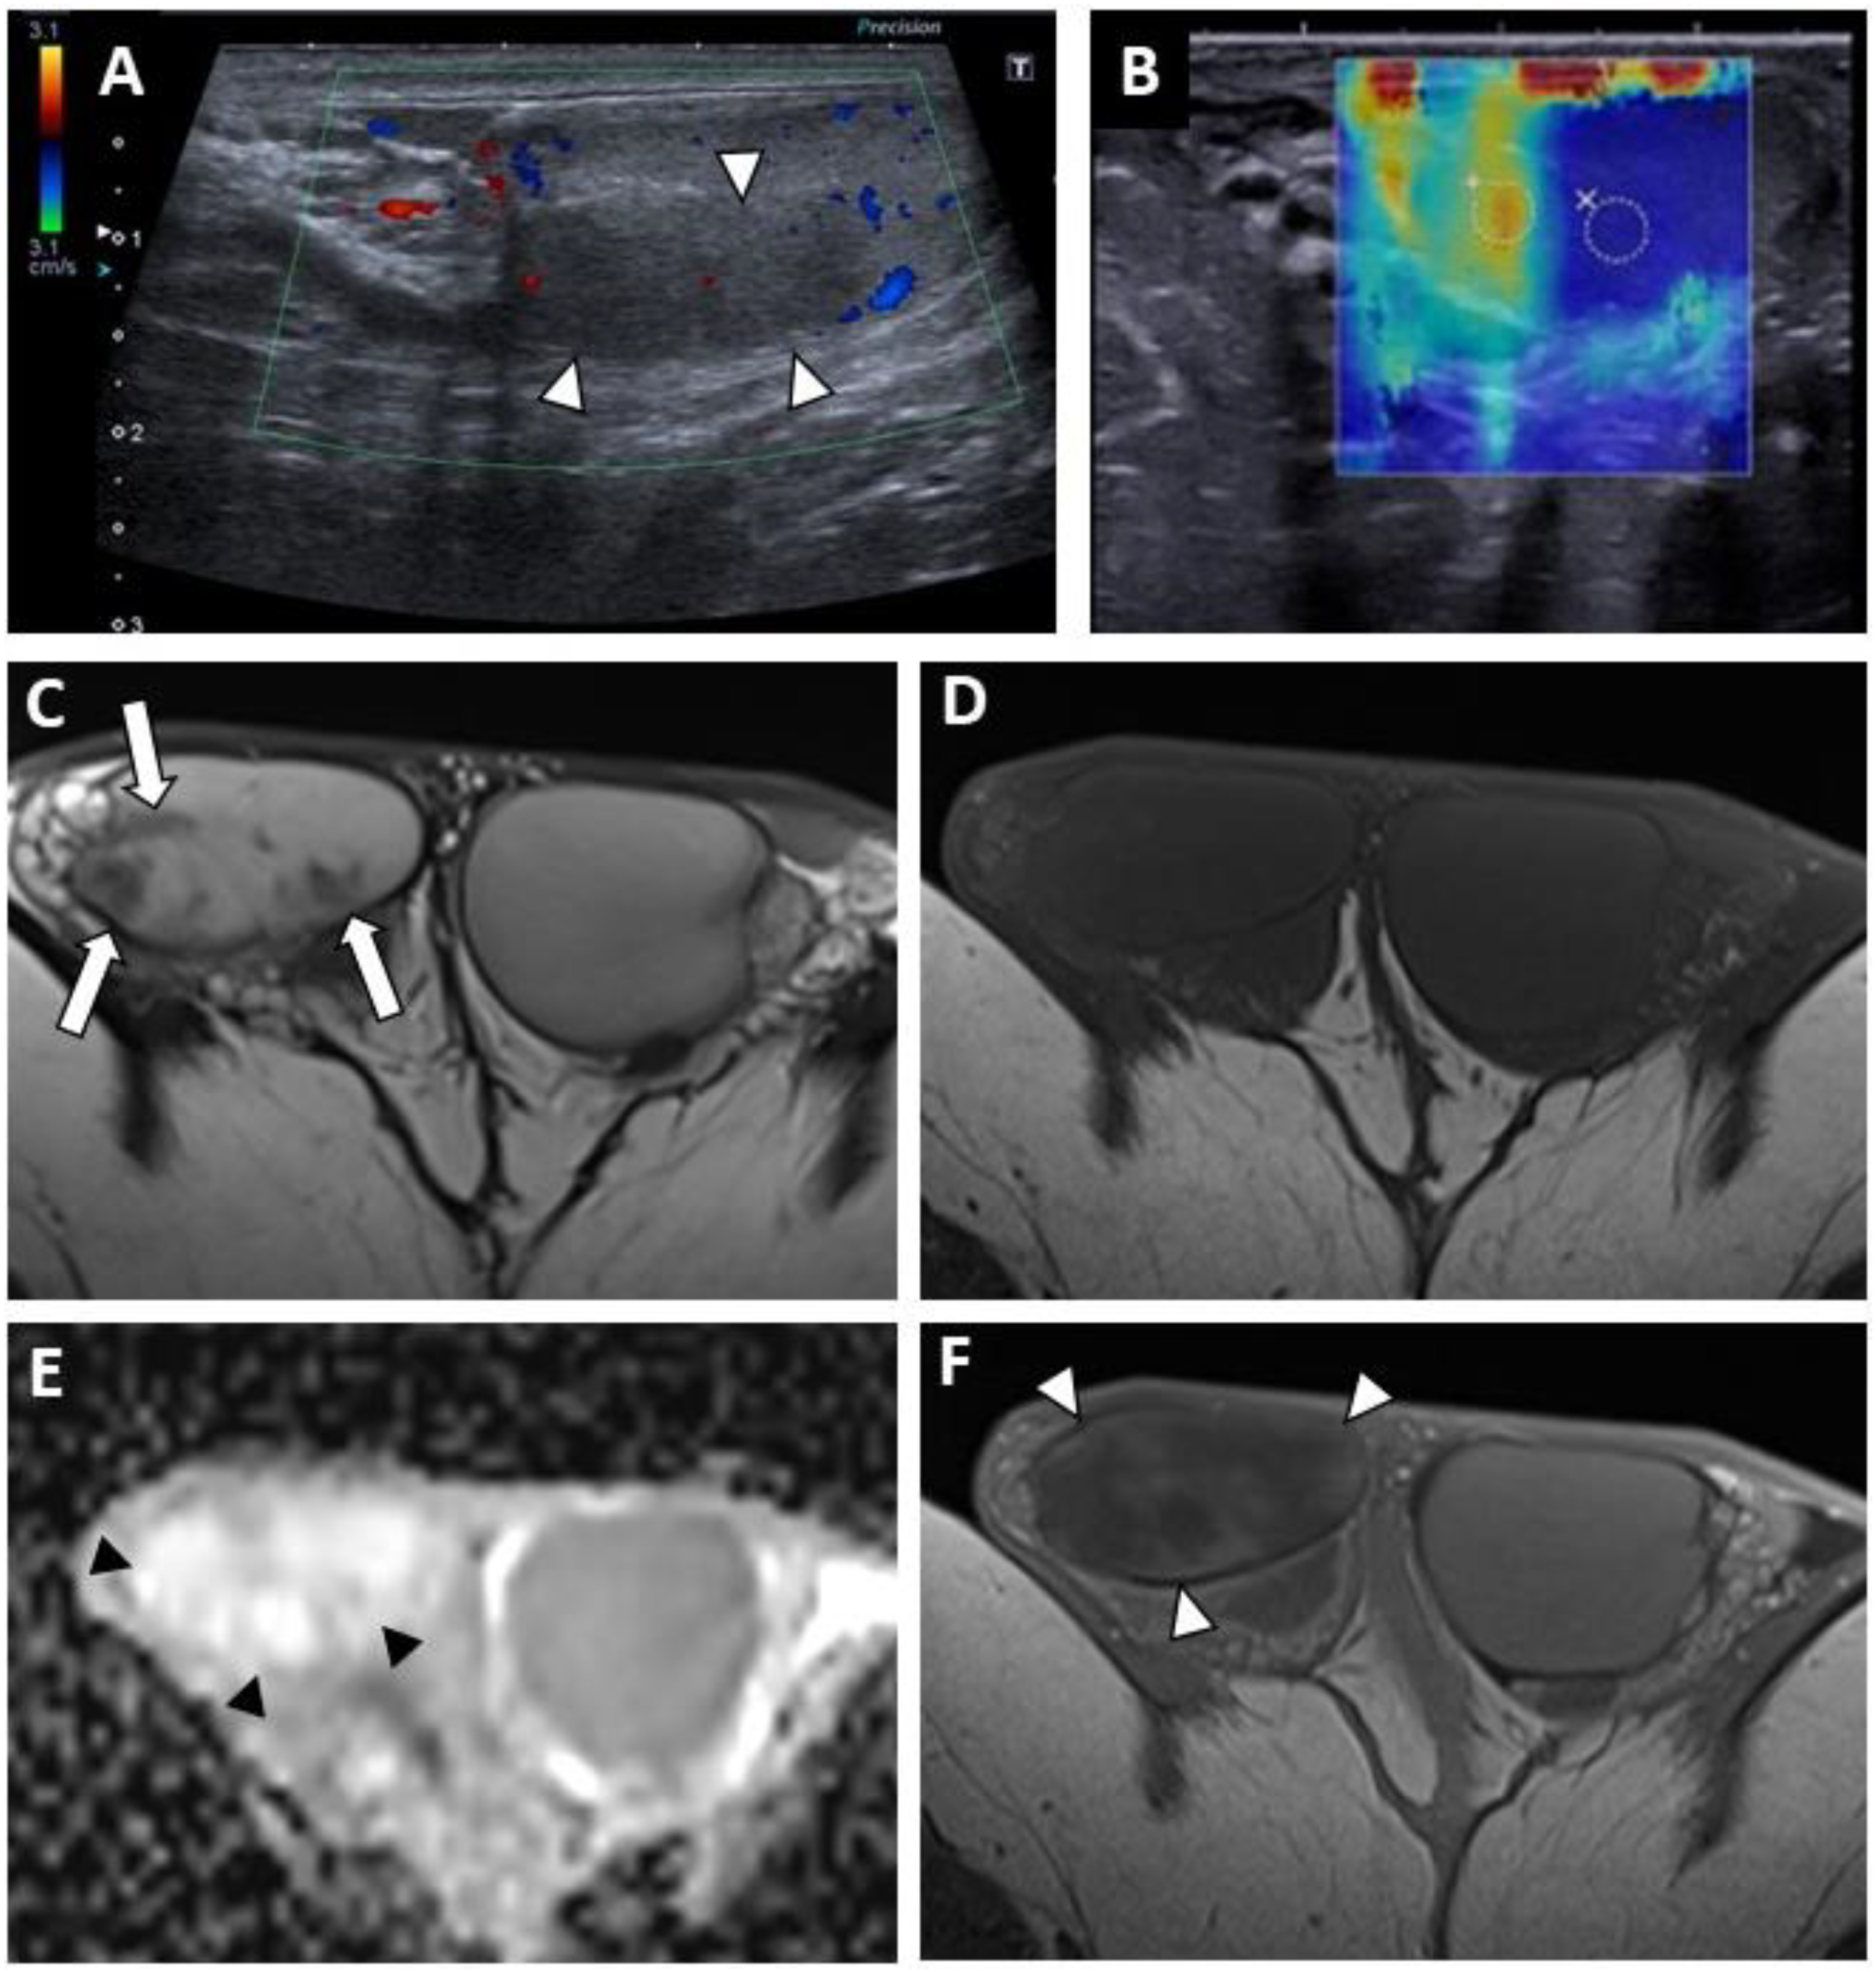

Figure 2. BOTT of the right testis in a 40-year-old man (symptomatic retroperitoneal nodes). Longitudinal image of US on Colour Doppler mode showing poorly circumscribed hypoechoic and hypovascularised nodular areas (white arrowheads) (A). Shear-wave elastography mapping showed a focal induration (B) (different slice plane from image (A)). Axial T2W image showed multiple irregular areas with a hypo-intense signal (white arrows) (C). Axial T1W image without a detectable focal lesion (D). ADC map of the diffusion sequence demonstrated a focal area with an elevated ADC value compared with the contralateral testis (black arrowheads) (E). After the intravenous injection of gadolinium chelate, confluent areas with reduced enhancement were visible (note that these areas are overlapping the nodules visualized in T2) (F).